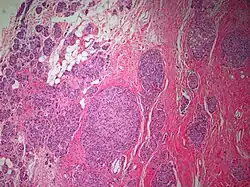

The microscopic histopathology of PACB tumors prepared with hematoxylin and eosin staining shows that >90% of the tumors consist of apocrine gland-like tissue. The lesions must also show that tumor cells have broken through their ducts of origin to invade adjacent tissue in at least one area. Most of the tumor cells (termed type A cells[15]) typically appear somewhat more irregular than normal apocrine gland cells. They have abundant eosinophilic (i.e. pink due to the uptake of the eosin dye) cytoplasm which contain numerous granules[11] and large mitochondria.[15] Their nuclei are large, variably sized and shaped, have multiple nucleoli (which are eosinophilic[11] and may be distinctively large in size[14]), and are surrounded by highly visible nuclear membranes. The cells are arranged into solid sheets, nests, papillae, and/or cords (see Figs. 1 and 2).[11] The tumor cells' cytoplasmic granules test positive when treated with the PAS diastase stain.[16] Binucleated cells, i.e. cells with two nuclei, are common.[10] Less commonly, type B apocrine cells are present; these cells have a more foamy and vacuolated cytoplasm (i.e. containing multiple vacuoles) than type A cells[15] and often resemble foamy histiocytes or sebaceous gland cells.[17] The tumor cells have low to moderate rates of proliferation based on their Ki-67 protein levels.[7] PACB tissues may have localized areas that contain mucin-like secretions within their luminal ducts,[10] localized areas of necrosis (i.e. foci containing dead or dying cells), and/or microcalcifications spotted throughout the apocrine tissue.[11] The stroma (i.e. connective tissue between the sheets, nests, papilla and cords of cells) typically contains non-malignant, infiltrating lymphocytes (see Fig. 3). In an examination of 41 PABC tumors, 33 (80.5%) had <50% of their stroma tissues infiltrated with these cells while 8 (19.5%) had ≥50% of their stroma tissues infiltrated with them. Tumors with ≥50% of their stroma infiltrated with lymphocytes tended to have carcinoma cells that had high rates of proliferation.[11] Metastatic and recurrent PACB tumors have a histopathology similar to their original primary tumors.[14]